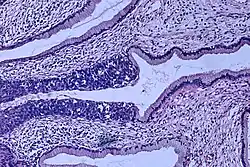

Histopathologic image (H&E stain) of carcinoma in situ (also called CIN3), stage 0: The normal architecture of stratified squamous epithelium is replaced by irregular cells that extend throughout its full thickness. Normal columnar epithelium is also seen.

Cervical intraepithelial neoplasia (CIN) means the development of abnormal cells on the surface of the cervix. HPV infections cause CIN, but in most cases, it is resolved by the immune system. However, a small percentage of people might develop a more serious CIN, which, if left untreated, can develop into cervical cancer.[66][67] CIN is often diagnosed during routine Pap smear examination or colposcopy.[67]

The naming and histologic classification of cervical carcinoma precursor lesions has changed many times over the 20th century. The World Health Organization classification system was descriptive of the lesions, naming them mild, moderate, or severe dysplasia or carcinoma in situ (CIS).[68][69] The term cervical intraepithelial neoplasia (CIN) was developed to place emphasis on the spectrum of abnormality in these lesions and to help standardize treatment.[69] For premalignant dysplastic changes, cervical intraepithelial neoplasia grading (CIN 1–3) is used. It classifies mild dysplasia as CIN1, moderate dysplasia as CIN2, and severe dysplasia and CIS as CIN3.[70] More recently, CIN2 and CIN3 have been combined into CIN2/3. These results are what a pathologist might report from a biopsy.